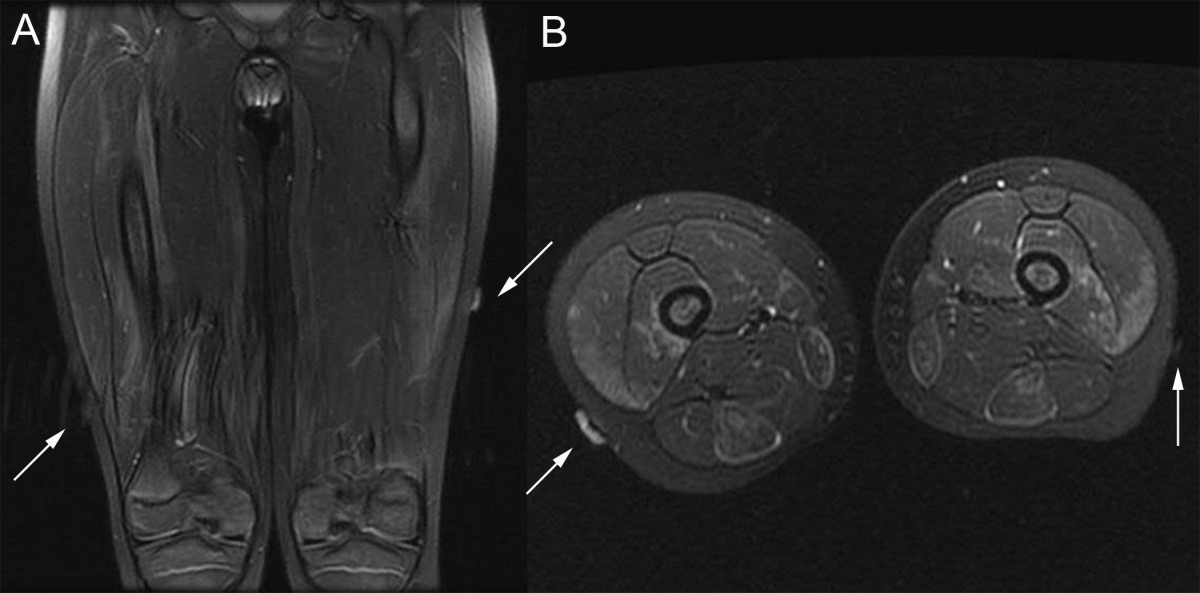

From ped-rheum.biomedcentral.com

MRI guided wire localization muscle biopsy in a child with juvenile Wire Guided Biopsy You may also hear this called a wire guided wide. this test is used when your doctor wants to take a sample of breast tissue (biopsy) but needs help to pinpoint the abnormal. This type of biopsy is performed when you have an abnormality seen on a. if a mammogram or breast ultrasound reveals an abnormality that can't. Wire Guided Biopsy.